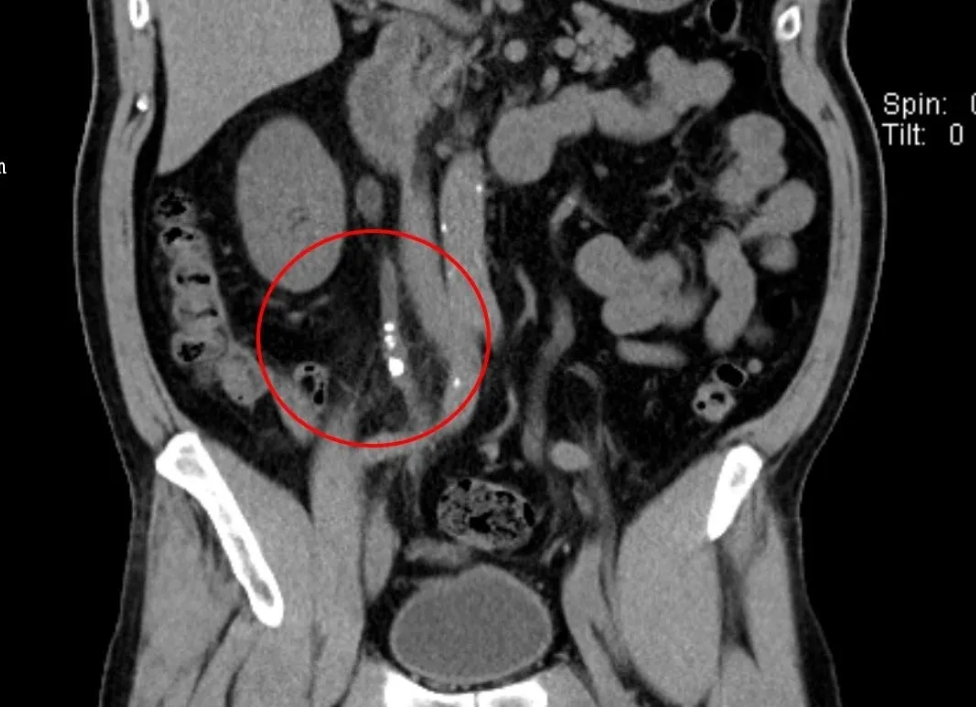

近日,我院成功为一名因双侧输尿管结石完全梗阻,导致急性肾功能衰竭的患者实施“双侧输尿管镜同期手术”,将患者肾功能从崩溃边缘拉回。经过精心治疗,患者肾功能已恢复正常,目前状态良好。60岁的谢先生,因突发右侧腰部绞痛到我院泌尿外科门诊就诊。经检查发现,谢先生双侧输尿管中段结石完全梗阻,这是典型的"石头堵死生命通道"!双肾出现重度积水,已达"红色警戒线"。肾盂扩张超3cm且皮质变薄。同时已发展为急性肾功能衰竭,肌酐值超过526μmol/L(男性正常值:54—106 μmol/L),尿素达18.1mmol/L(成人正常值:2.5—7.1 mmol/L)。

面对复杂的病情,我院泌尿外科副主任雷鸣迅速组织多学科会诊,经过详细讨论,科室团队一直认为,患者双侧输尿管结石和双肾积水是导致急性肾功能衰竭的主要原因,必须尽快手术解除梗阻,恢复肾脏功能。考虑到谢先生的肌酐值太高,为了稳定其内环境,先进行血液透析,再实施手术解除梗阻更妥。经过血液透析,使肌酐值降至300μmol/L,为后续手术争取了宝贵时间。为避免二次创伤,泌尿外科决定采用“双侧输尿管镜同期手术”方案,一次解决双侧梗阻。术前,通过CT三维重建技术精准定位结石位置,并根据透析后患者身体状况评估手术耐受性。术中,雷鸣带领泌尿外科团队为谢先生实施了经尿道输尿管软镜右侧输尿管激光碎石取石+经尿道输尿管硬镜左侧输尿管激光碎石取石术。运用双镜联合技术,超细输尿管硬镜与软镜协同操作,硬镜快速疏通近端梗阻,软镜处理肾盂残留结石;使用钬激光将双侧结石逐层粉末化,并通过负压吸出碎屑,有效避免术后“石街”形成;术后留置双侧双J管,保障输尿管通畅,促进肾功能恢复。